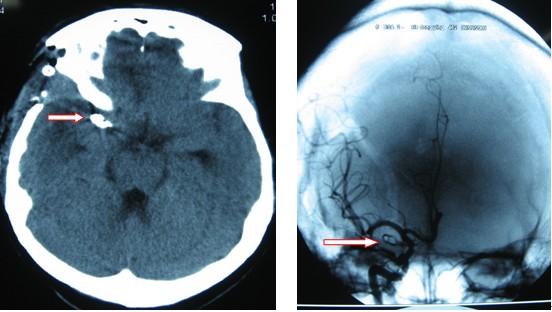

病例1:謝冬英,女,45歲,永定區人,因右眼下垂、復視3年,加重伴頭痛1周入院,入院后患者出現嚴重腦血管痙攣、導致右側肢體癱瘓。CT檢查發現自發性蛛網膜下腔出血,DSA檢查發現右側后交通動脈瘤,5×10mm大小,瘤體壓迫右側動眼神經。2009年8月23日行右側后交通動脈瘤顯微夾閉手術,術后患者逐漸康復,目前患者右側動眼神經麻痹恢復,右惻肢體肌力4級,生活基本自理。復查DSA,患者動脈瘤夾閉完全。

病例2:吳光付,男,53歲,病程:突發神志不清1天入院,入院時淺昏迷,GCS:E1V3M4=8分,頭顱CT:廣泛蛛網膜下腔出血,右側外側裂血腫。DSA檢查發現右側大腦中分叉部動脈瘤,4×5mm大小。2009年10月18日行右側大腦中分叉部動脈瘤顯微夾閉手術,目前患者神清,正在積極康復鍛煉。因經濟原因暫未復查DSA。

圖一:術前CT示蛛網膜下腔出血(箭頭所指) 圖二:術前腦血管痙攣至腦梗塞(箭頭所指)

圖六:術后CT可見腦內動脈瘤夾 圖七:術后DSA檢查可見腦內動脈瘤夾